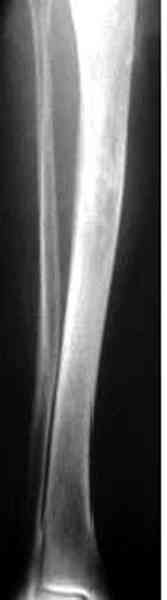

Недавно на нашей ежемесячной Morbidity&Mortality

conference мы разбирали похожий случай, ложный сустав большеберцовой кости после резекции опухоли.

К нашему онкологу-ортопеду обратился больной с жалобами на боли в голени, из рассказа - год назад была сделана биопсия большеберцовой кости, но название заболевания "не запомнил”.

Оперирован в военном госпитале с заменой сегмента

аллокостью большеберцовой кости и после демобилизации явился для постоянного наблюдения по месту жительства.

В литературе "A Classic Adamantinoma Arising from

Osteofibrous Displasialike Adamantinoma in the Lower Leg: A case report and Review of the Literature похожие снимки.

Наши имели проблему со сращением, пришлось им сделать динамизацию, дополнительную аутопластику.

Снимки представлены.